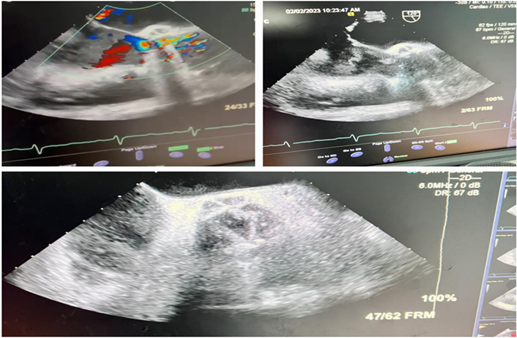

Computed tomography scan

of thorax, abdomen, and pelvis did not show any source of infection. A

trans-thoracic echocardiogram showed mild aortic regurgitation and mitral

regurgitation with no clear vegetation, however, trans-esophageal

echocardiogram (TEE) showed reduced left ventricular function with moderate

central aortic regurgitation. Hypoechogenic mass along the aortic side of the

mechanical aortic valve was noted. Important paravalvular leak and non-coronary

sinus abscess was suspected (Figure 2).

Figure 2. Transesophageal echocardiography findings Red

arrows-abscess